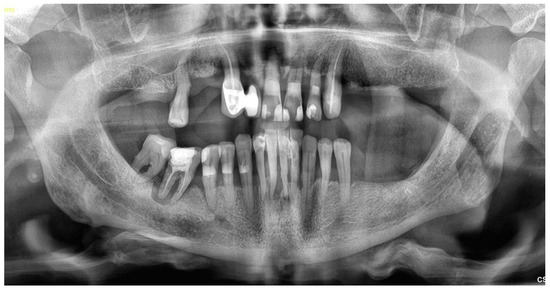

2.1. Patient Information and Clinical Findings

- Intraoral scan and CBCT;

- The merging of the abovementioned examination data and design of the prosthetically driven implant positions.